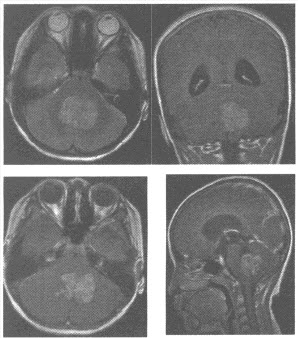

男性,66岁,因头痛、左侧肢体无力3天来诊。血压:165/95mmHg。颅脑MRI扫描如下图,应诊断为()

A:胶质母细胞瘤

B:脑血肿

C:脑挫裂伤

D:海绵状血管瘤

E:动静脉畸形